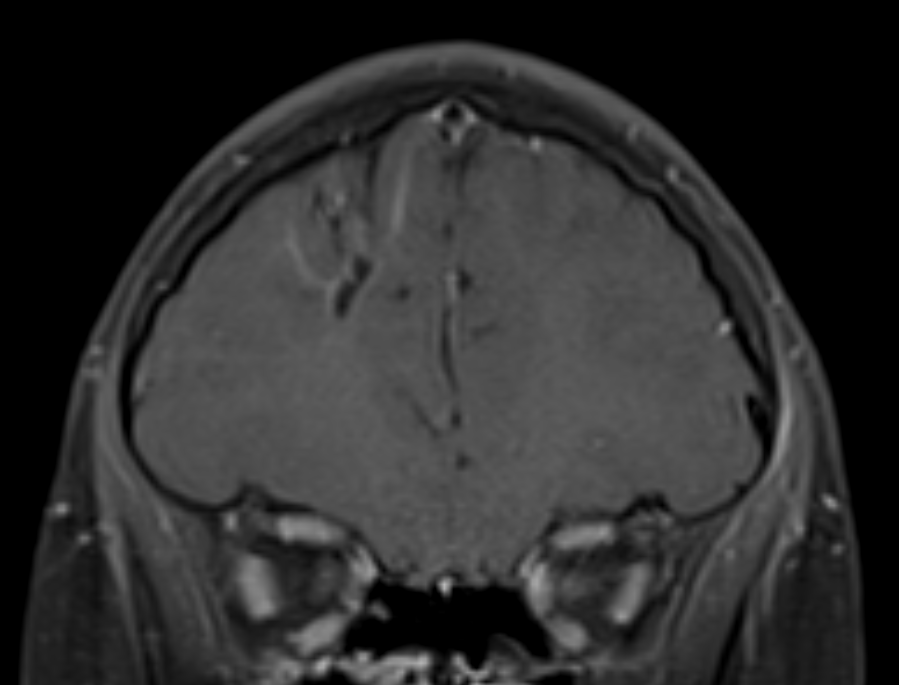

IPNTN: Rupa Radhakrishnan from Riley Children's highlights potential uses for ASL and DSC in pediatric neuroimaging with cases of hemiplegic migraine (ASL) and tumor recurrence (DSC). #IPNTN #PedRad #pedineurorad

This week’s #SPIN-#POV brought to you by an incredibly intelligent spinner Sniya Sudhakar. When you spot the nodular and curvilinear perisylvian heterotopia, think of a problem with the centrosomes. This ones an example of CEP135 mutation. We are collecting these folks, RSVP!